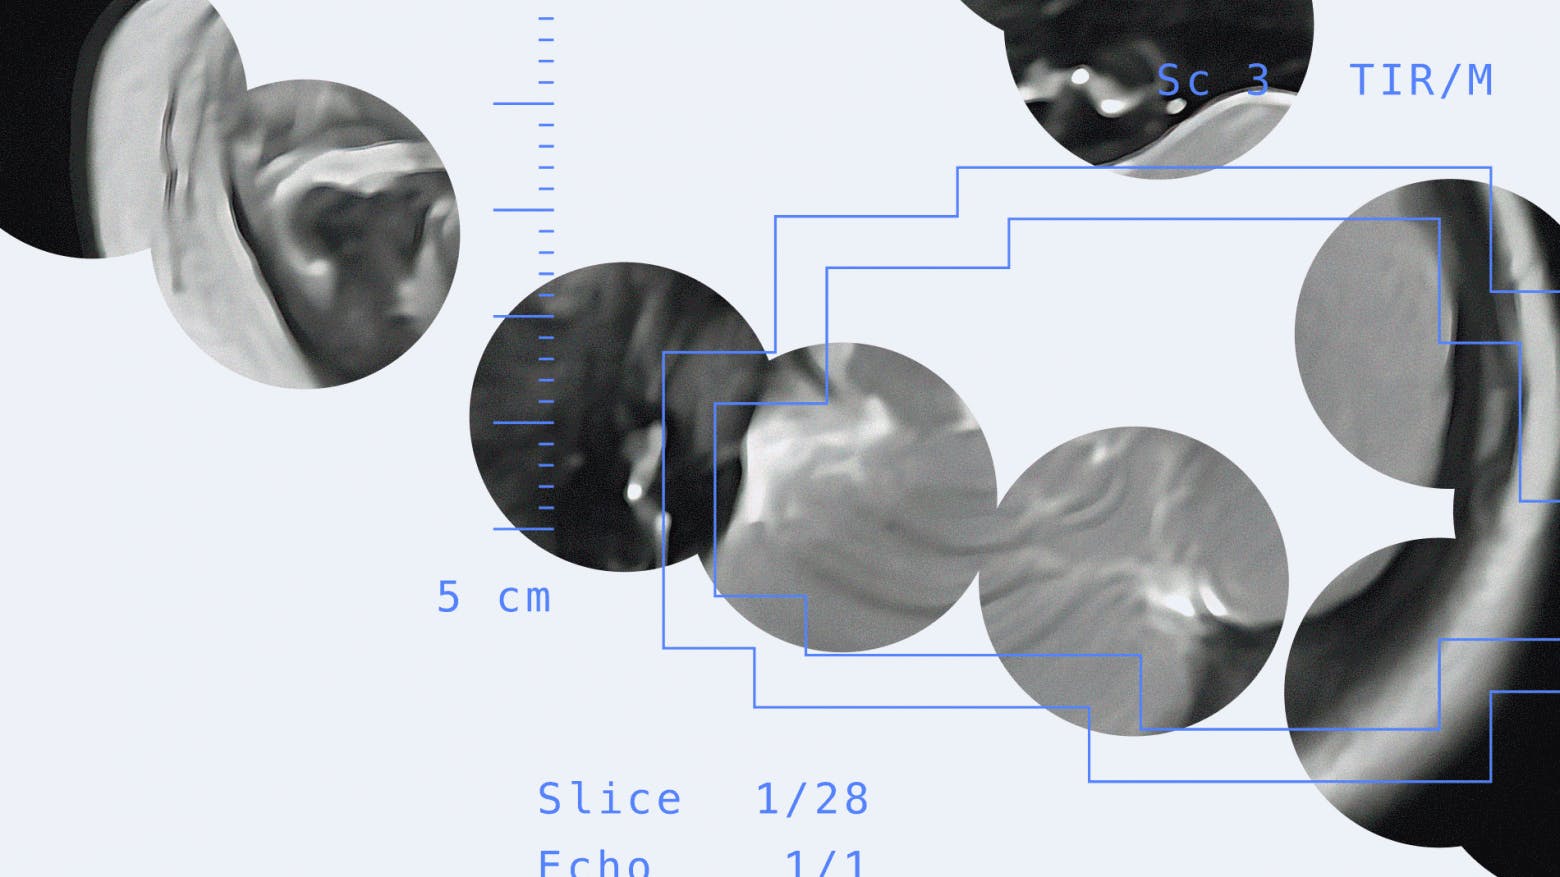

Here's how the model performs on the validation set. Original study from the validation set:

Example output from the algorithm

The solution automatically identifies gray matter and white matter areas on each MRI slice, providing predictions with confidence scores.

The service is primarily morphometric, meaning it measures tissue volumes. Once processing is complete, users see the model's predicted volumes of gray matter, white matter, and cerebrospinal fluid, along with descriptions of the largest structures.

From the summary table, you can select a specific study to view the scan with the white matter and gray matter masks applied.